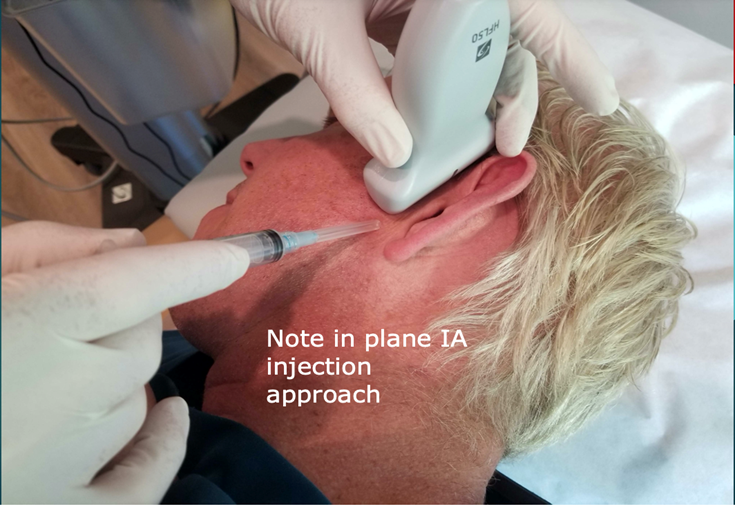

Scanning Technique. For the intra-articular injection, the patient is placed in a side-lying position with the head turned to the opposite side. The high-frequency linear transducer is placed in a coronal orientation. (Figure 3).

Figure 3: Scanning technique. The patient is placed in a side-lying position with the head turned to the opposite side. The high-frequency 15-6 MHz linear transducer is placed in a coronal orientation.